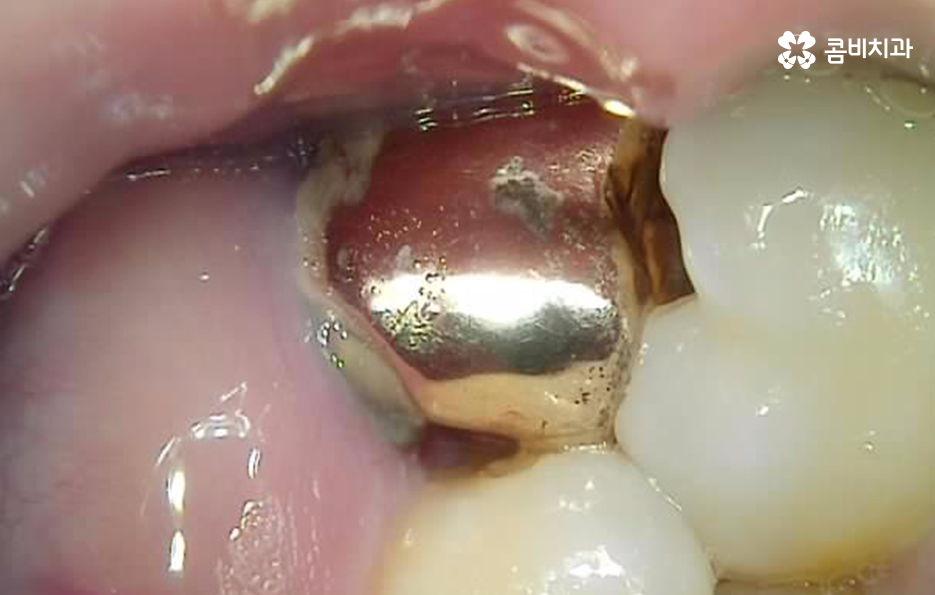

하지만 위 사진에서 보시는 것처럼 치아에서 통증은 못느끼더라도 2차 충치가 발생되어 뒤늦게 치아 내부의 충치에 대해 알게 되면 이미 치아 뿌리까지 충치가 심각하게 진행되어 크라운 재치료가 어려울 정도로 손상이 진행된 경우도 많으며 결국 어금니 발치후 임플란트 치료로 이어질 수 있어요

신경치료 후 크라운을 씌우게 되었더라도 치아의 뿌리 손상 정도와 치아의 잔존량에 따라서 크라운의 재치료, 즉 재신경치료와 같은 방법으로 자연치아를 보존하는 방법도 있지만 치료 시기를 놓치게 된다면 어금니 발치후 임플란트 시술을 받아야 하기 때문에 오래된 보철물은 주기적으로 검진을 통해 필요하다면 재치료 시기를 놓치지 마시길 바라고 있어요

위 치료 사례의 경우 크라운 내부의 2차 충치로 인해 치아 발치를 진행한 사례이기 때문에 치아 상실의 원인이 충치인 경우에는 잇몸 뼈의 상태 자체는 양호한 경우가 많이 있는데요